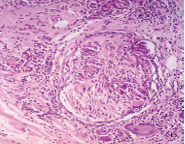

Figure 4a This nerve is surrounded by granulomas and lymphocytes but its structure looks normal.

Figure 4b It is not easy to determine if this nerve is being infiltrated and destroyed by the cellular reaction or if it is simply surrounded by it.

Figure 4c Well preserved nerve with a giant cell, scant macrophages and some lymphocytes in the endoneurium. A-C: HE. A,10 X. B, 16 X. C, 40 X.

Some giant cells and macrophages touched the nerve or penetrate the endoneurium and distorted neural architecture (Figures 3,4). Other cutaneous nerves were located at the center of the infiltrate and looked well preserved (Figure 5).

Figure 5 These nerve bundle, located at the center of the granulomatous infiltrate, looks quite normal. This image is improper of leprosy. HE, 20X.